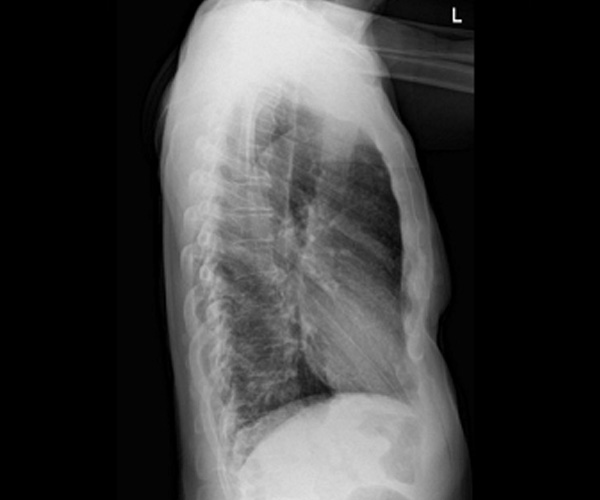

Dopo 3 giorni dalla dimissione si ripresentava in Pronto Soccorso per ricomparsa di febbre. Il tampone antigenico per COVID-19 risultava negativo, mentre l’Rx torace evidenziava l’aumento del disegno interstiziale (Figure 1 e 2).

Figura 2. Rx torace laterale

In alcuni pazienti con infezione disseminata da BCG, la radiografia del torace o la tomografia computerizzata (TC) mostrano un pattern nodulare o interstiziale miliare, talvolta associato ad adenopatia ilare; questi rilievi sono osservati più frequentemente in associazione con sepsi [10,45]. La sensibilità della radiografia del torace è limitata; in una serie comprendente 216 pazienti con infezione sistemica da BCG, la radiografia del torace non è riuscita a rivelare un pattern miliare in circa il 25% dei pazienti con polmonite successivamente identificata tramite TC [8].